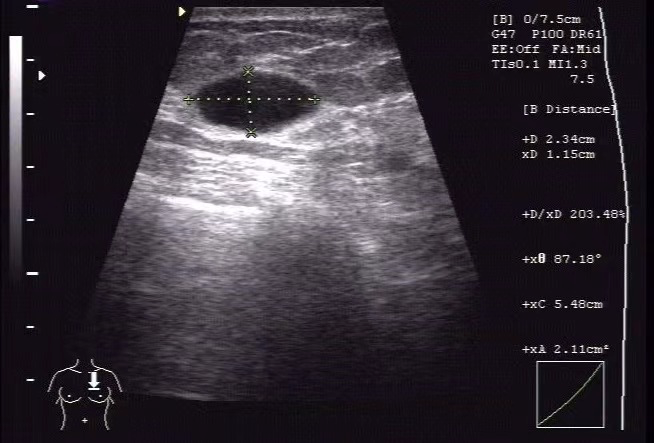

再來説説乳腺囊腫。

簡單來説,乳腺囊腫就是乳腺裏面長了一個「水泡兒」。

一般而言,乳腺囊腫是一個光滑的、容易移動的圓形或橢圓形腫塊,有可能自己摸得到,也有可能摸不到。

雖然只是個小水泡兒,但它會不會有一天突然癌變?

不必過度驚慌,乳腺囊腫是良性的乳腺病變,如果及時發現和治療,癌變的可能性很小。

但也不能完全不管,不僅要堅持複查,還要隨時觀察乳房的變化。